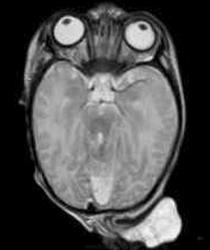

Менингоэнцефалоцеле

Энцефалоцеле

Энцефалоцеле

Энцефалоцеле

Фронто-этмоидальное энцефалоцеле

Цефалоцеле